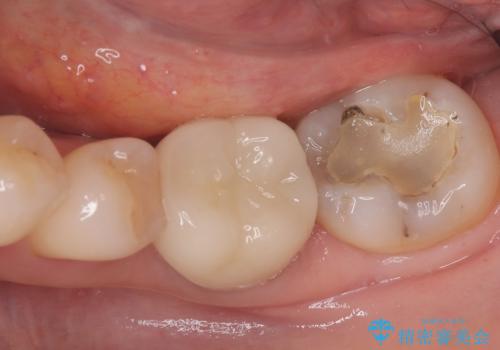

セラミッククラウンによる奥歯の修復

担当医 河口智英